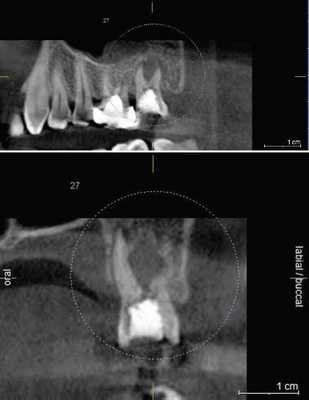

КЛКТ найдено применение конкретно при диагностике перелома корня зубов.

(Фото 7,8) Высокая важность КЛКТ в определении вертикальных и горизонтальных переломов корня были также описаны в литературе. Элиминация наложения анатомических структур позволяет клиницисту четко анализировать перелом. Вдобавок, 3D реконструкция может быть осуществлена как зубочелюстной системы, так и альвеолярной кости.

Фото 7: Перелом корня в эндодонтически леченом верхнем правом втором моляре

А: ОПГ, показывающая ранее леченые каналы верхнего правого первого моляра

B: Аксиальное изображение, демонстрирующее линию перелома по небному корню

С: Секционный снимок, показывающий косую линию перелома небного корня

Фото 8: горизонтальный перелом правого верхнего центрального моляра

А: 3D изображение, демонстрирующее линию перелома у соединения средней и апикальной трети корня

B: Аксиальный снимок, показывающий горизонтальную линию перелома в передней части верхнего правого центрального резца

С: Косая линия отлома, распространяющаяся от мезиального каря центрального резца на секционном снимке.